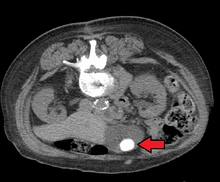

Images of a CT of gallstones

Large gallstone